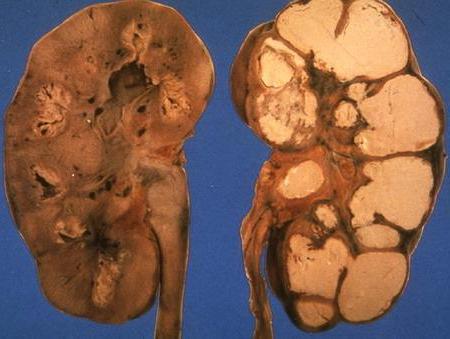

![]() Рис. 2. Туберкульозна каверна в нирці. |

Туберкульозний процес, викликаючи руйнування нирки, що призводить до утворення каверн в нирці (рис. 2), туберкульозних виразок слизової оболонки миски та сечоводу, які, піддаючись рубцюванню, порушують відтік сечі з нирки. Далеко зайшов туберкульоз нирки може призвести до утворення туберкульозного піонефрозу (див.).